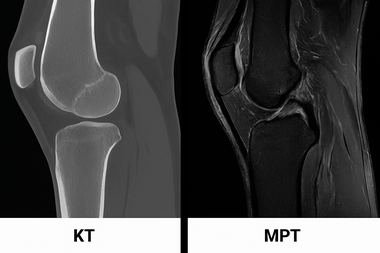

Рентген, УЗИ или МРТ: в чем разница

Чтобы понять цель МРТ, нужно разобраться, чем оно отличается от других методов. Каждый из них решает свои задачи, и они не всегда могут заменить друг друга:

Рентген. Это «специалист» по костям. Он идеально показывает переломы, вывихи, трещины или грубые изменения формы сустава при артрозе. Но мягкие ткани — мениски, связки, хрящи — рентгеновские лучи проходят насквозь. На снимке вместо них врач видит лишь пустоту или едва заметные тени. Оценить их состояние по рентгену невозможно.

УЗИ. Хорошо показывает мягкие ткани, но имеет физические ограничения. Ультразвуковая волна не может пройти сквозь кость, поэтому заглянуть в самый центр сустава или посмотреть, что находится за костью, не получится. Глубокие структуры остаются в «слепой зоне».

МРТ. Дает максимально полные данные. Томограф сканирует колено послойно — буквально по миллиметру, в разных проекциях. Врач получает не плоский снимок, а объемную картину. Видно абсолютно все: структуру хряща, целостность глубоких крестообразных связок, состояние костного мозга, нервов и сосудов.